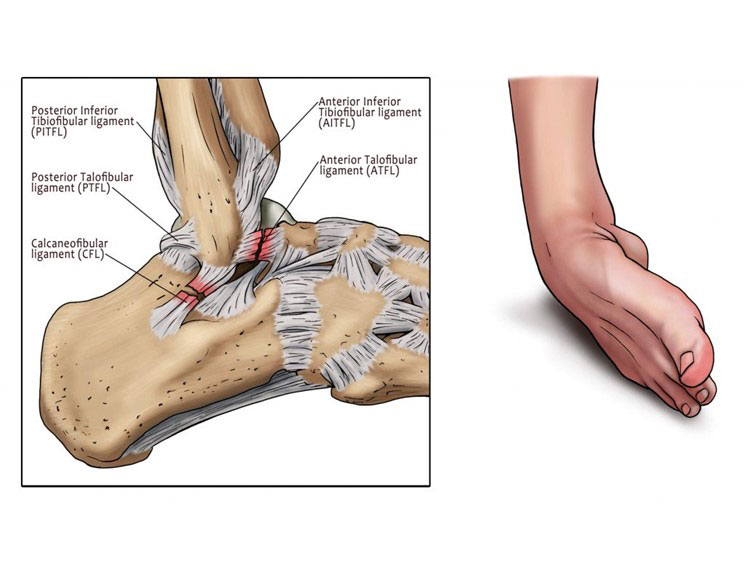

Lateral Ankle Sprain Motus Physical Therapy